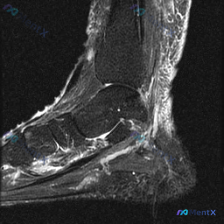

给大家分享一份足部矢状位T2加权MRI的读片分析,原始问题是询问图像中观察到的软骨异常,整理一下完整的分析思路:

这份MRI可见胫骨远端、距骨、跟骨、舟骨、楔骨及部分跖骨,踝关节、距下关节及跗骨间关节对位基本正常,关节面轮廓完整,没有明确骨质破坏或骨折线,跟腱走行和信号都正常。

核心的异常表现其实集中在足底:

- 跟骨附着点处的足底筋膜明显增厚,T2信号增高

- 跟骨下方软组织,尤其是足底筋膜起点周围和皮下软组织,都有信号增高的水肿改变,提示局部炎性反应

第一眼看到这个影像表现,最典型的就是足底筋膜炎,符合的点非常明确:足底筋膜增厚+附着点周围水肿,跟骨下方软组织炎性改变,这都是足底筋膜炎的经典影像学特征。

但原始问题明确提到了「软骨异常」,我们不能只抓着最典型的表现不放,得把这个线索也纳入分析。